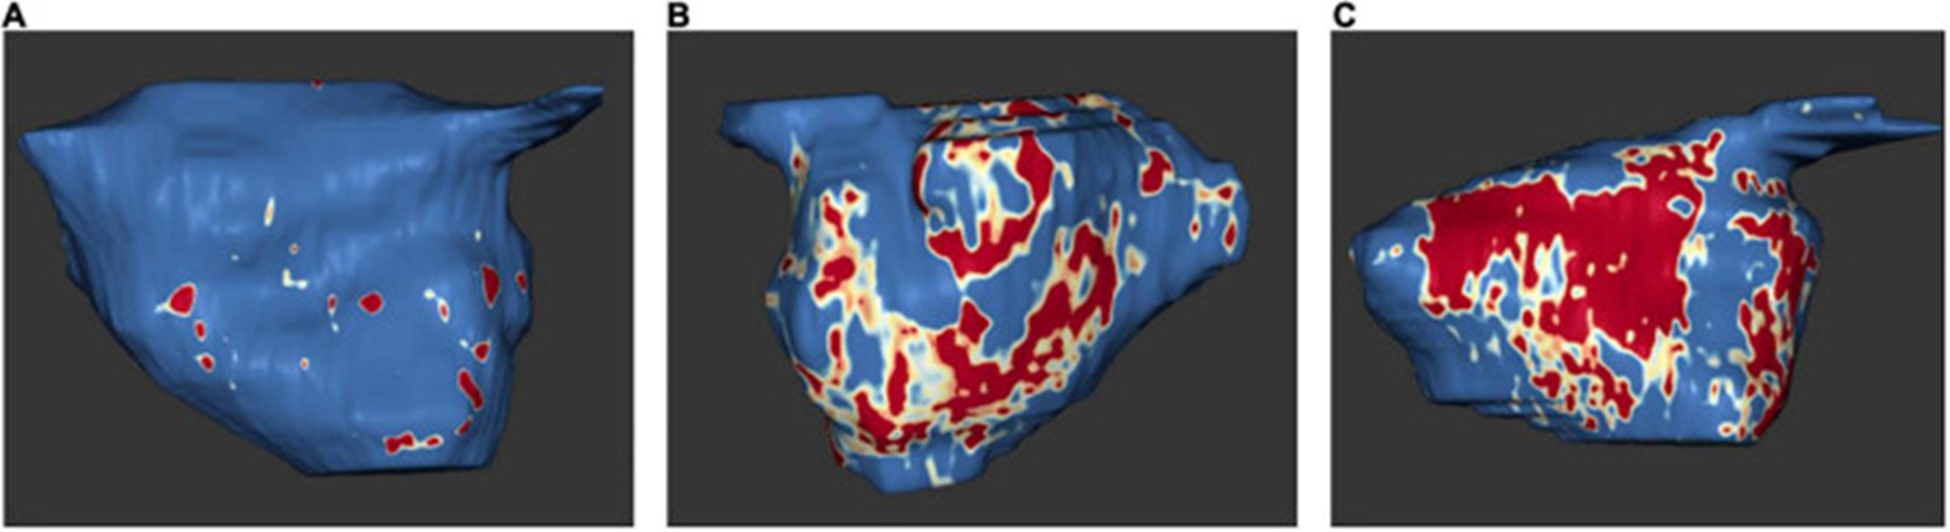

2009 年,Oakes 等人。建立了犹他阶段模型来量化 LA 纤维化 。根据该模型,将严重程度分为四个级别:犹他州 I,定义为 ≤ 5% LA 壁增强,犹他州 II,5–20%,犹他州 III,20–35%,犹他州 IV,>35% (图 5)。

图 5:左心房 MRI 检查示例:基于 3D 延迟增强磁共振成像扫描的左心房组织纤维化。正常左心房壁以蓝色显示,纤维化改变以红色和白色显示。纤维化量占左心房壁总体积的百分比。(A)犹他州第一阶段 (1%)。(B)犹他州第 3 阶段 (27%)。(C)犹他州第 4 阶段 (36%)。在 Misagh Piran 博士(Herz- und Diabeteszentrum Nordrhein-Westfalen,Ruhr-Universität Bochum)的友好支持下。

延迟增强 MRI 与来自 LA 结构重塑的手术活检组织学之间发现了高度相关性,包括间质和脂肪纤维化以及总纤维化和脂肪 。原生 T1 对应于 MRI 和组织学的纤维化程度 。此外,与没有 AF 的患者相比,AF 患者的 LA 壁增强似乎更大(77)。

延迟增强 MRI 发现的 LA 瘢痕区域与心内膜标测中的低电压区域有关 。

由于 LA 晚期钆增强与 LA 射血分数和超声心动图左室间隔 e' 和室间隔 E/e' 之间存在显着相关性,因此更高量的 LA 晚期钆增强与 LA 功能下降以及 LV 舒张功能下降有关(79)。斑点追踪超声心动图也证明了延迟增强和 LA 功能降低之间的相关性。延迟增强 MRI 测量的 LA 壁纤维化程度与斑点追踪超声心动图显示的 LA 应变和应变率之间存在反比效应,特别是 LA 中外侧应变和应变率(80)。有趣的是,与阵发性 AF 患者相比,持续性 AF 患者出现更多的纤维化和更少的中间隔和中外侧应变 。一般来说,新发房性心律失常的风险随着 LA 晚期钆增强量的增加而增加 。

既往卒中患者和卒中高危患者(表现为 CHA2DS2-VASc 评分高)在延迟增强 MRI 中 LA 纤维化的比例显着增加。LA 纤维化是脑血管事件的独立预测因子,显着提高了 CHA2DS2-VASc 评分的预测能力 。上升的犹他阶段和更强烈的 LA 晚期钆增强与主要心血管事件的风险增加有关,主要是由于中风或 TIA 的风险增加(82)。有趣的是,与 AF 患者相比,ESUS 患者的心房纤维化程度相似,这支持了纤维化是缺血性卒中和左心房心肌病的主要危险因素的假设(83)。